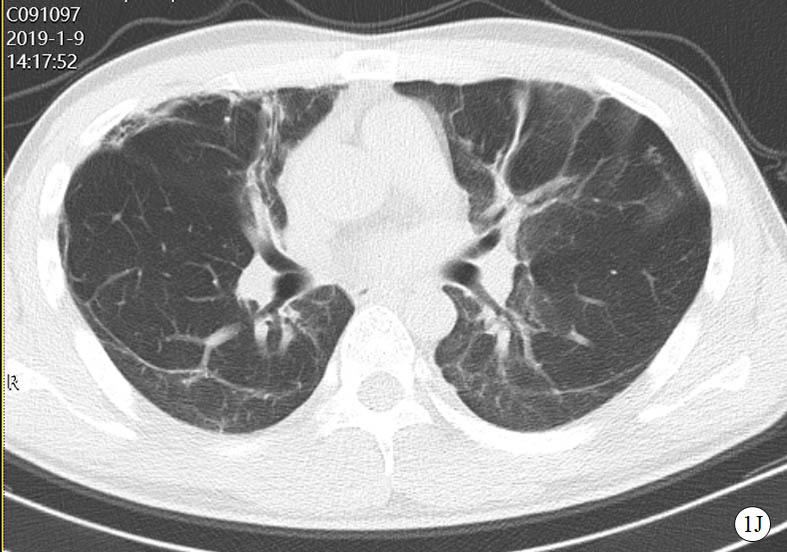

图 1 患者口服百草枯后胸部CT影像学变化

2019-01-09 CT图

2019-07-18 CT图